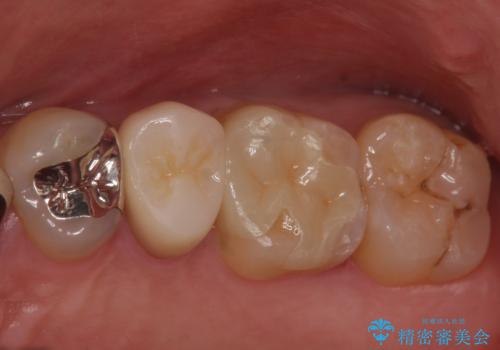

ご希望に沿って、ゴールドインレーにて治療を行いました。

- PGA(ゴールド)インレー 6.6万円 × 2本費用は治療当時の料金となります

ゴールドインレーは適合がよく、強度もあり、腐食もしにくく、アレルギーのリスクが極めて少ない安定した治療法です。虫歯の再発リスクを減らすことができます。